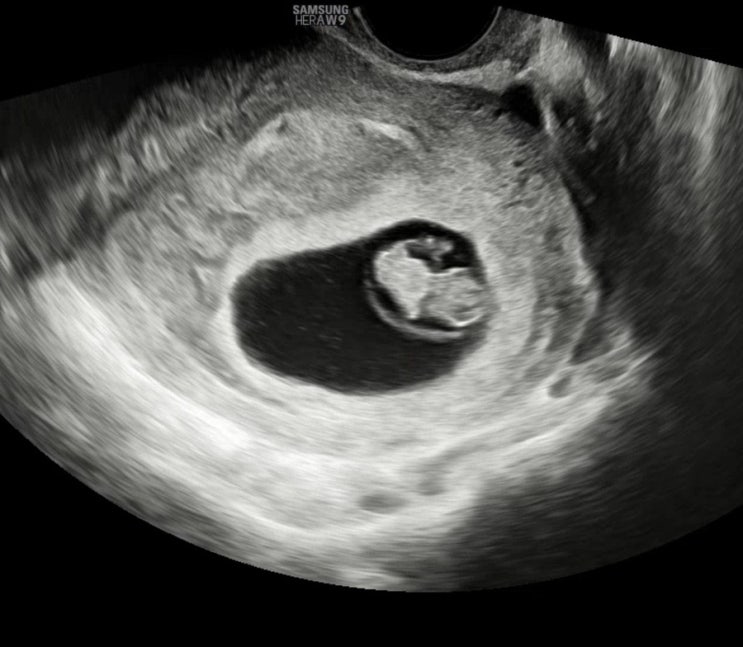

임신일기#3. 임신 11주차~임신16주차까지|태아보험 가입, 1-2차 혈액 기형아검사, 12주 정밀초음파, 입덧수액,16주 아기성별확인, 아인병원 기형아검사 결과확인

임신 11주 - 16주의 기록 임신 11주차 입덧이 여기서 더 심해질수 있나 싶었는데 더 심해짐 물 한모금 삼키...

임신일기#2. 임신 5주차~임신10주차까지|첫 심장소리, 임신주수&예정일확정, 국민행복카드발급, 8주 젤리곰 확인, 산후조리원예약, 10주차 진료

임신 5주차부터 10주차까지의 일기 입덧때매 중간중간 병원간 기록도 제대로 못했지만 .. 임신 5주차 첫 아...